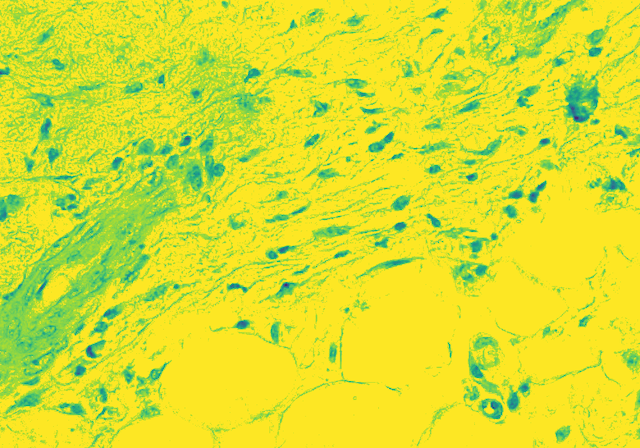

Histopathological Image Analysis of White Blood Cells

The project is to identify and count the White Blood Cells in a Skin Tissue. Firstly, we have to differentiate between RBCs, WBCs and Platelets. Not only that, we have to take into account, the presence of hair follicle in the skin sample. Then, WBCs have been identified, we have to further classify WBCs into their aforementioned types. The classification will be done on the basis of the number of nucleus in the types of WBCs. Lastly, the count can be categorized as to be within, above or below the normal count of 4,500 to 11,000 microliter. Thus, identifying whether or not the sample is infected or not.

Our new approach will be to dive into Fully Convolutional Neural Networks for the task of “Semantic Image Segmentation”. Semantic Image Segmentation is the task of segmenting an image and coloring the segmented parts with the color of the classification class. We will adopt the technique on biological data and first make a CNN to segment our image and then move forward with the semantic analysis task. Making it a 2 way process will help us deal with the difficulties step by step. This novel approach of segmenting on cell level with CNN is an experiment that may give unlikely result. We are exploring various other techniques side by side since the task is tedious and accuracy is highly important.